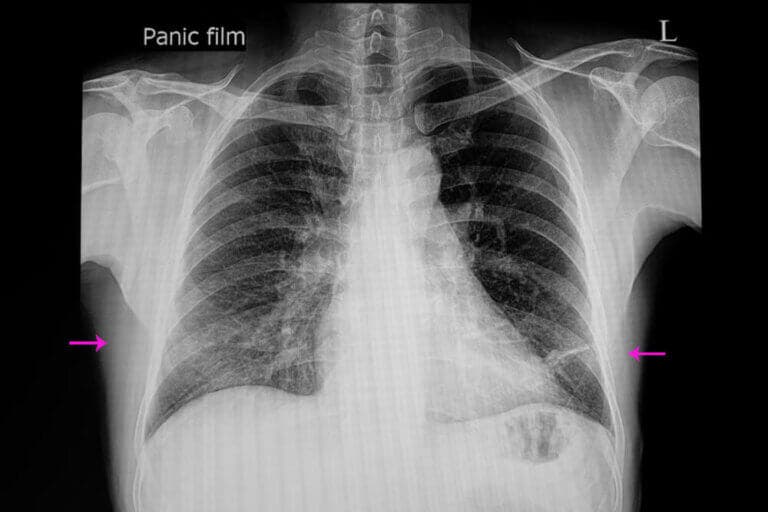

Para diagnosticar la atelectasia, suele bastar con una exploración clínica adecuada y una radiografía. Aún así, se pueden utilizar una serie de técnicas para confirmar el diagnóstico o medir la gravedad.